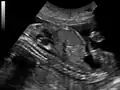

O ultrassom de feto mostrando o duto do Úraco da bexiga ao umbigo.